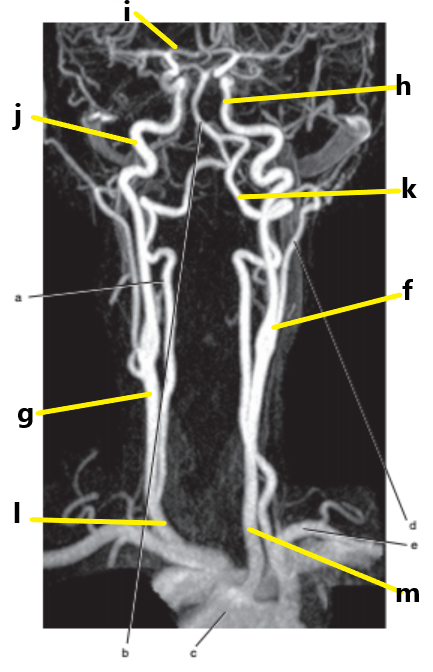

What is letter l ?

Common carotid

What is letter f ?

Common carotid artery

What is letter i ?

Anterior cerebral artery

What is letter m ?

What is letter j ?

Internal carotid artery

What is letter g ?

Vertebral artery

What is letter c ?

Aortic arch

What is letter b ?

External carotid artery

What is letter k ?

Subclavian artery

What is letter e ?

Carotid sinus/bifurcation